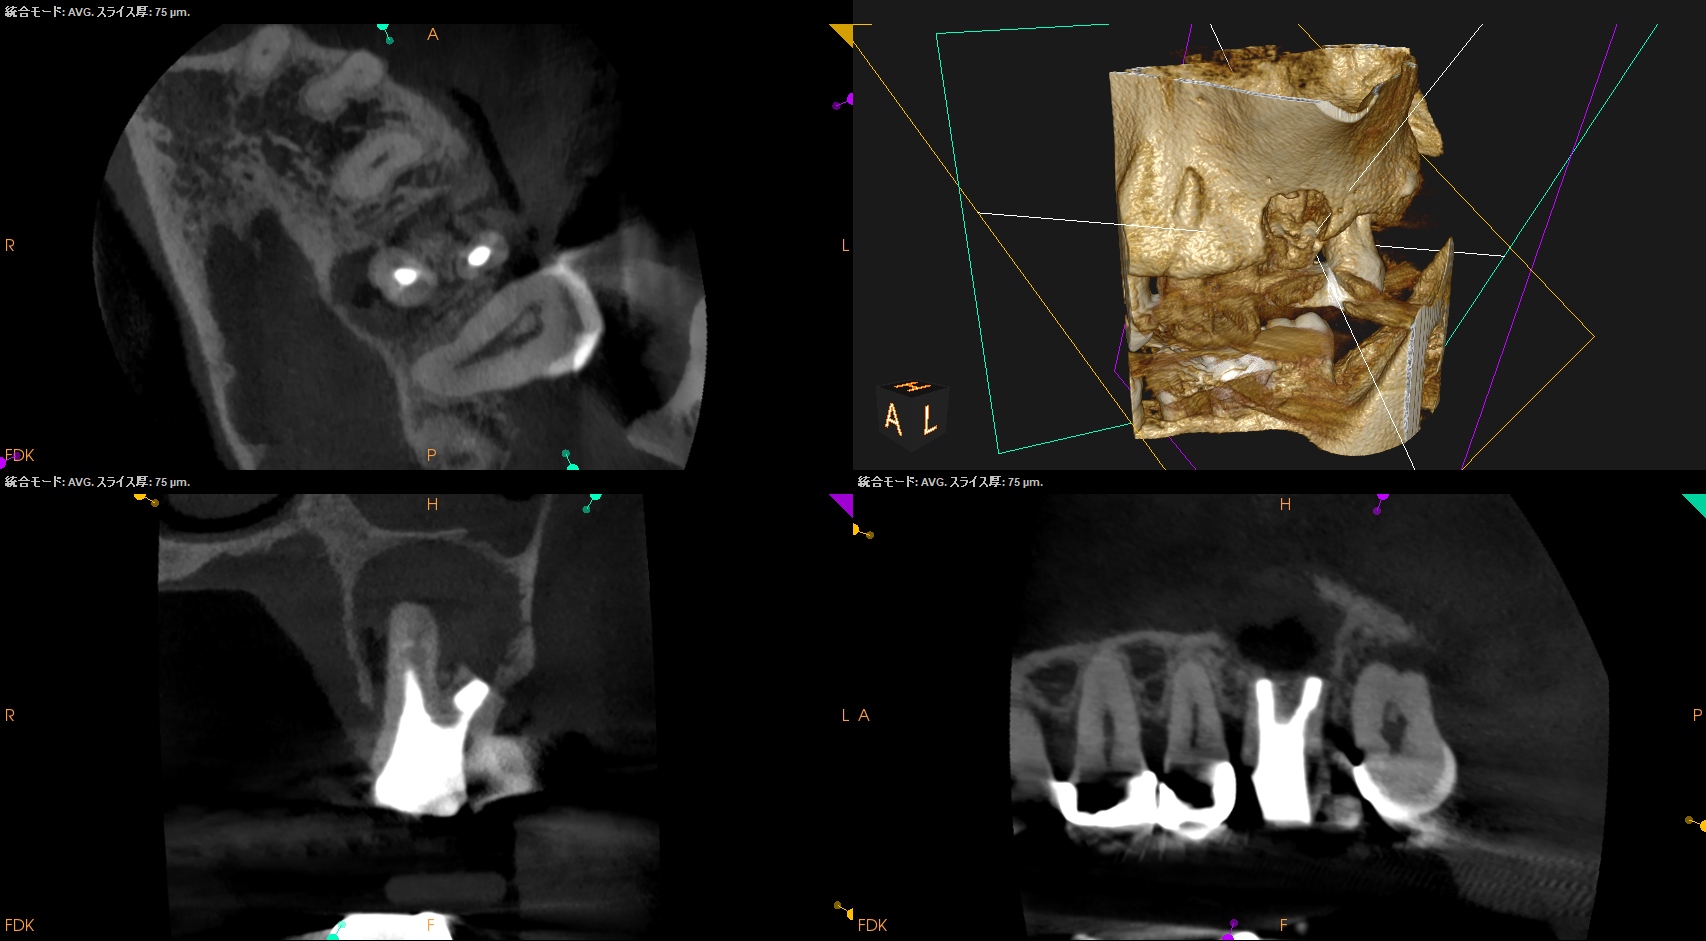

#14 Re-RCT(2023.6.20)

MB

DB

P

MB,DB,Pの3根全てに病変がある。